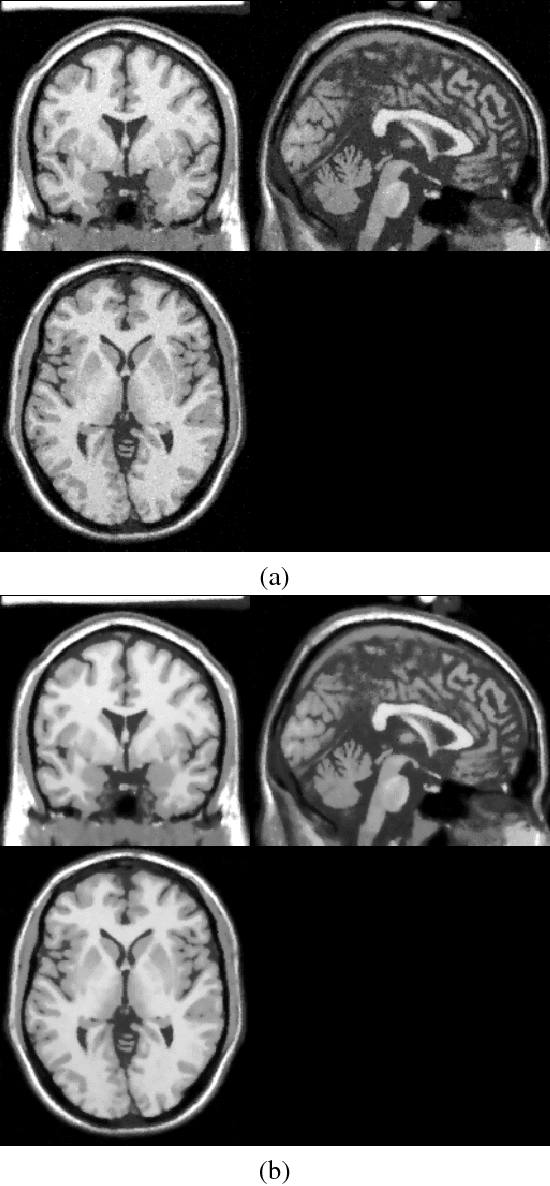

Abstract:High-frequency noise is present in several modalities of medical images. It originates from the acquisition process and may be related to the scanner configurations, the scanned body, or to other external factors. This way, prospective filters are an important tool to improve the image quality. In this paper, we propose a non-local weighted operational anisotropic diffusion filter and evaluate its effect on magnetic resonance images and on kV/CBCT radiotherapy images. We also provide a detailed analysis of non-local parameter settings. Results show that the new filter enhances previous local implementations and has potential application in radiotherapy treatments.